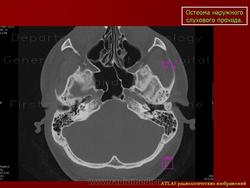

Остеома.

Приложения:

1.os_.slayd343.jpg2.os_.slayd344.jpg3.os_.slayd345.jpg